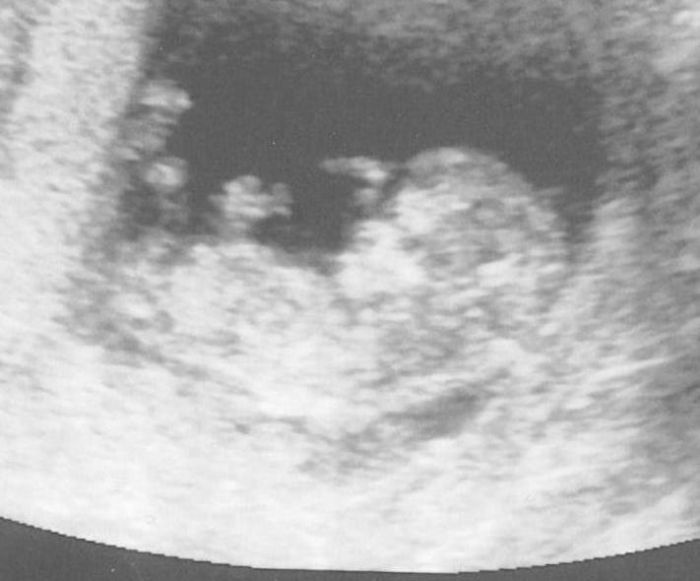

Jo a změnila jsem fotku, jistě si všimnete že je tam už vidět hlavička, tělíčko, ručička ale tu druhou schovalo asi a nožička. Je to vidět hezky.ale až to bude větší bude to vidět lépe.

[43039] anebo možná i obě dvě nožičky jsou vidět tak co holky mám zatím hezký mimčo a prý je zdravý i srdíčko je ok.